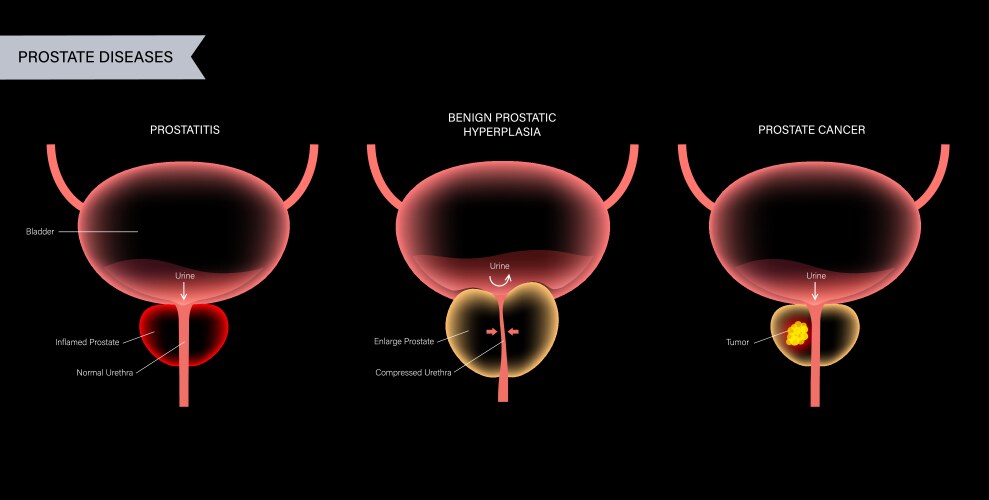

- Bph

- Prostate

- Anatomy

- Bladder

- Cancer

- Disease

- Prostatitis

- Tumor

- Gland

- Organ

- Types

- Urology

- Inflamed

- Urethra